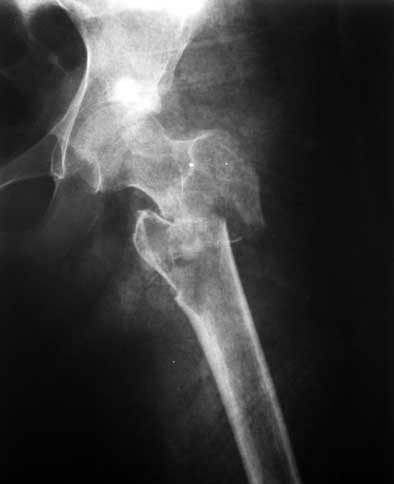

Коллеги,Полтора года назад девочке (сейчас ей 16) была сделана частичная резекция вертельной области с аутопластикой из гребня подвздошной кости.

На днях - патологический перелом (первый снимок). Пока наложена кокситная повязка (второй снимок). Вопрос - как лучше вести больную? Консервативно - оставить в этой же повязке? Остеосинтез? Какой именно? Спасибо. Екатерина А. Озерова, детская ортопедическая клиника УНИИТО